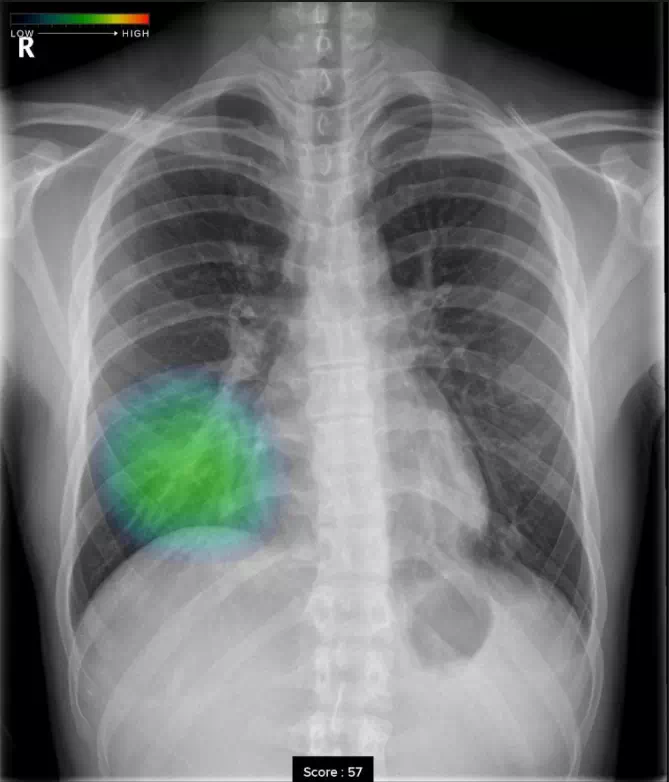

浸潤影

ヒートマップ表示機能

AIが異常の可能性がある領域を自動解析し、確信度に応じた表示を行います。確信度のスコアは0~100の範囲で設定され、画像上では色分けされたヒートマップとして示されます。

スコア表示機能

0~100の範囲で確信度スコアの最大値が数値として表示されます。